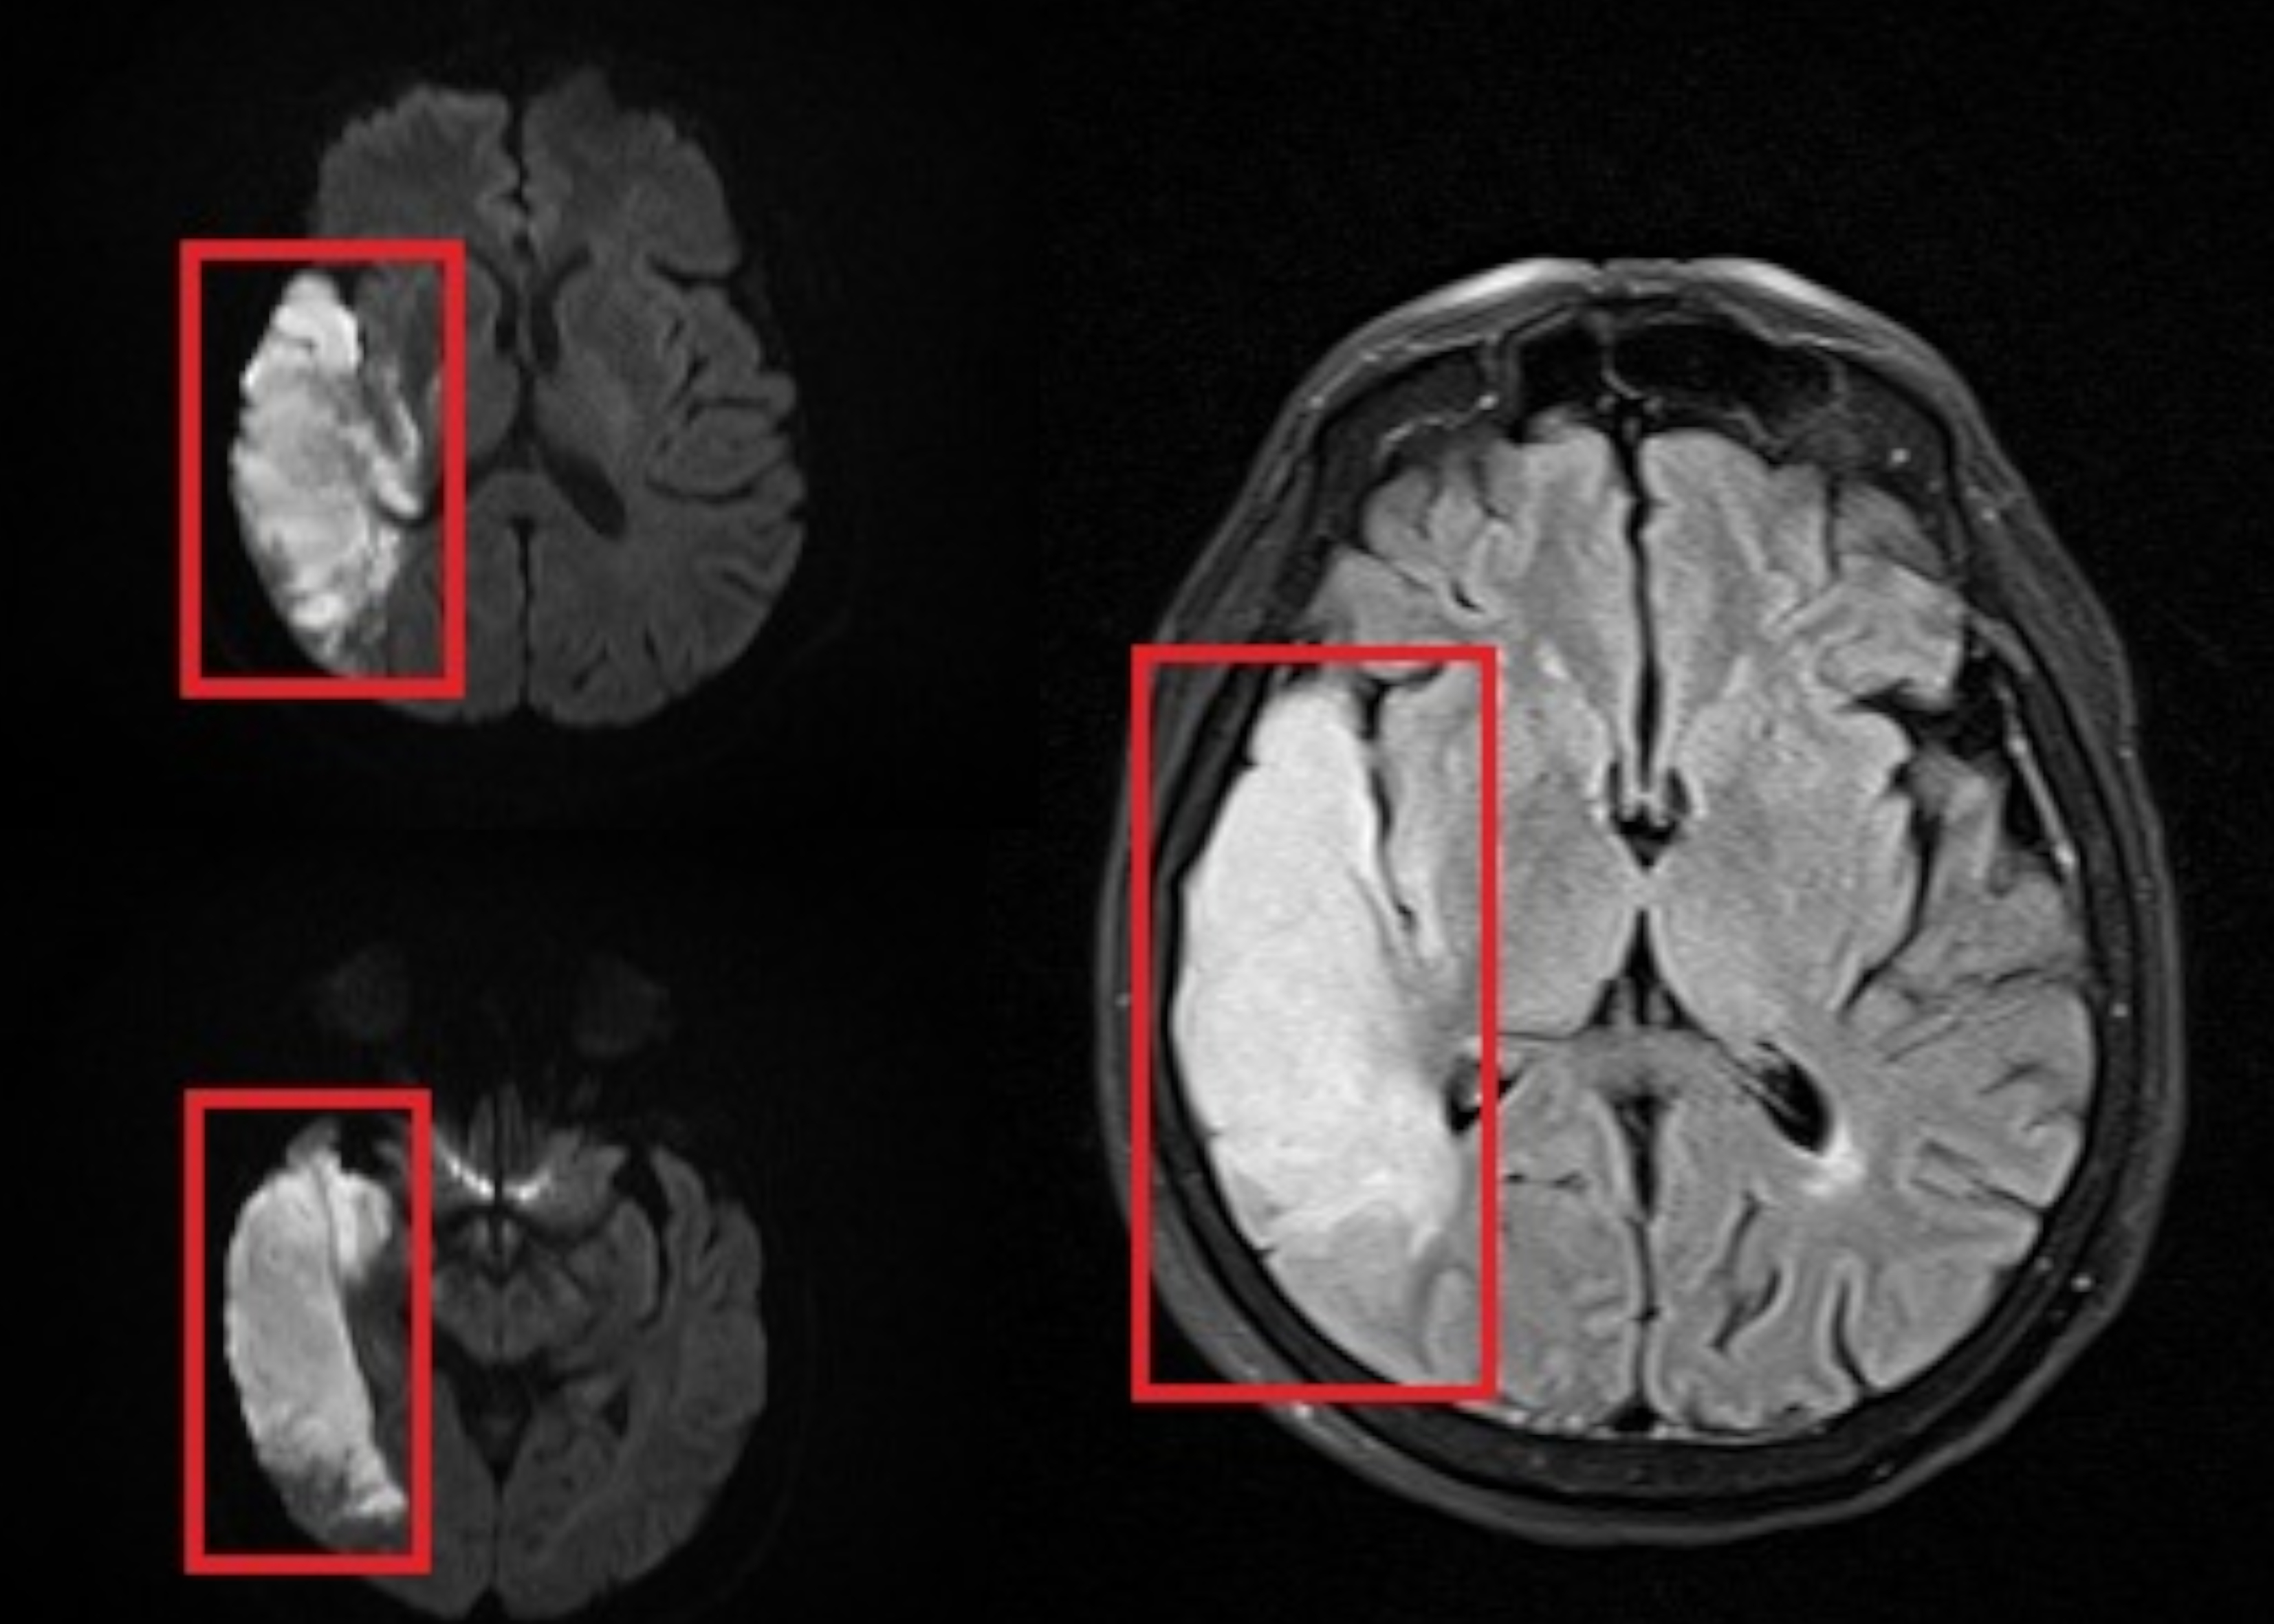

Hoy acudimos a tu sentir de amor al prójimo para apoyar a una persona muy querida que, tras sufrir un Accidente Cerebrovascular Isquémico nivel GRAVE (ACV), comprometiendo casi la totalidad del hemisferio derecho de su cerebro, enfrenta una condición de salud grave y totalmente dependiente, que ha cambiado su vida y la de su familia de manera drástica. Actualmente se encuentra postrada al 100% y requiere cuidados permanentes, atención médica constante y tratamientos especializados para poder mantenerse estable y con dignidad.